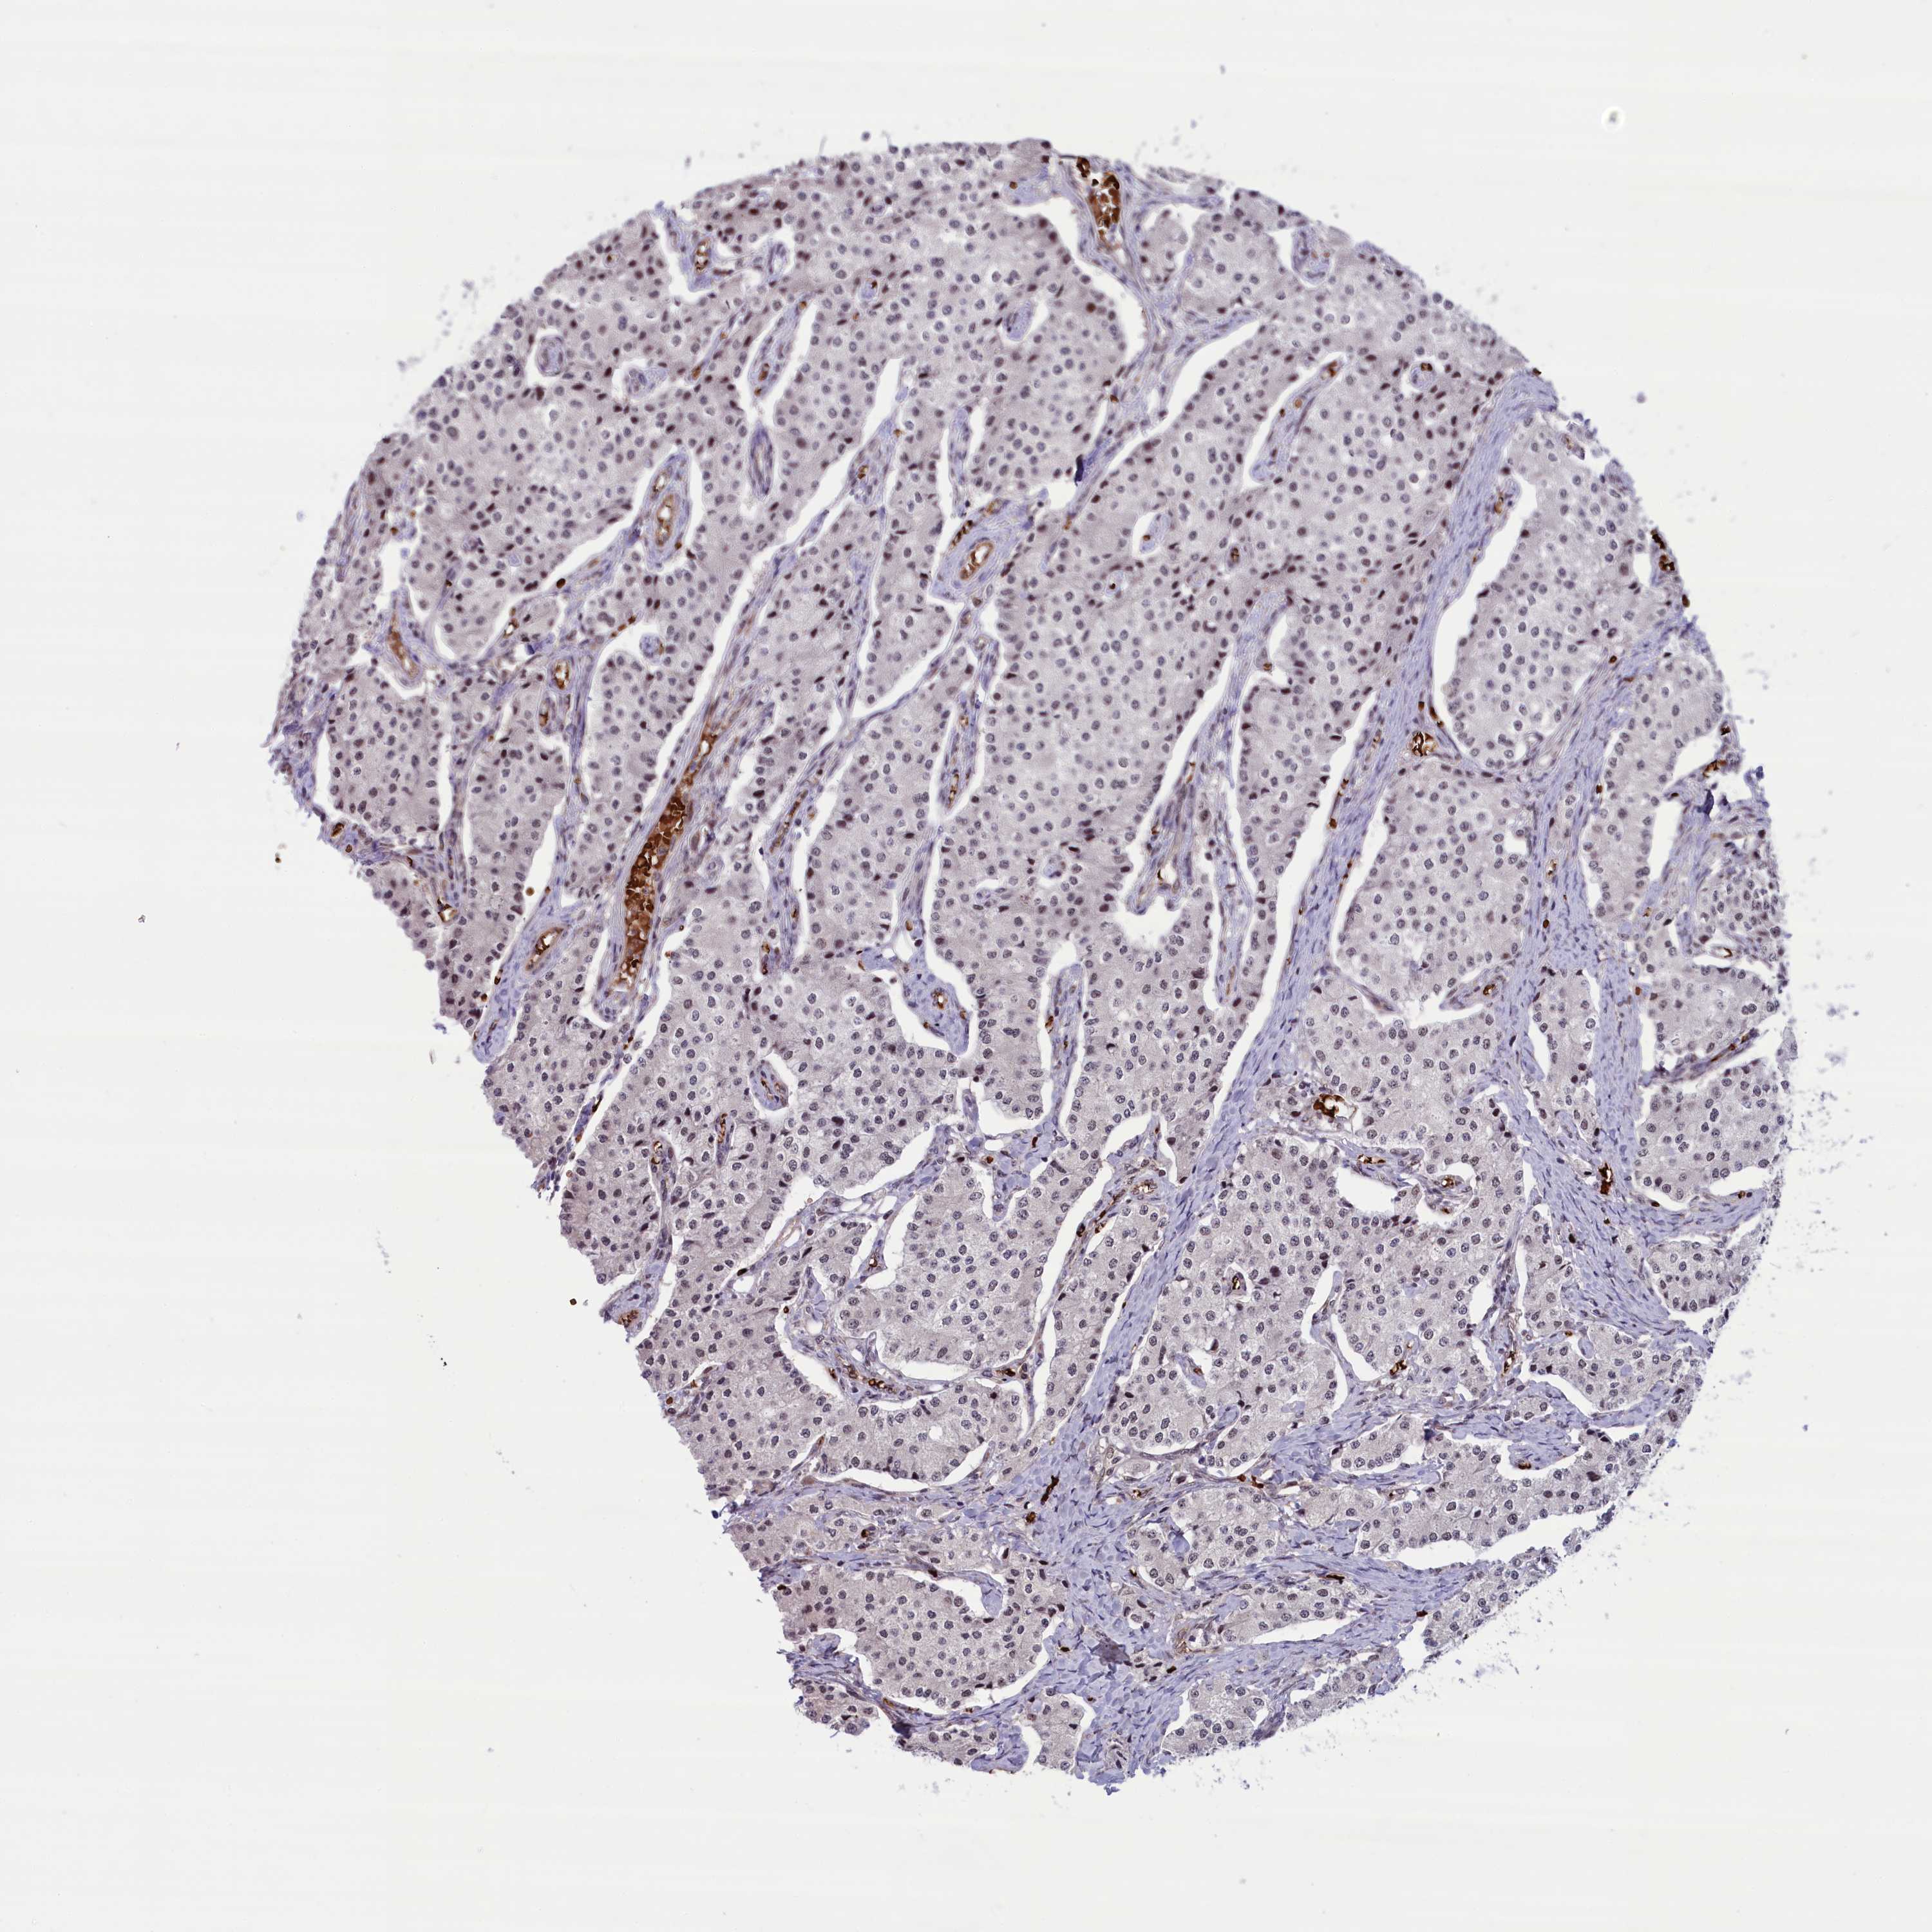

PATHOLOGY

CARCINOID

Neuroendocrine tumors

Human pathology